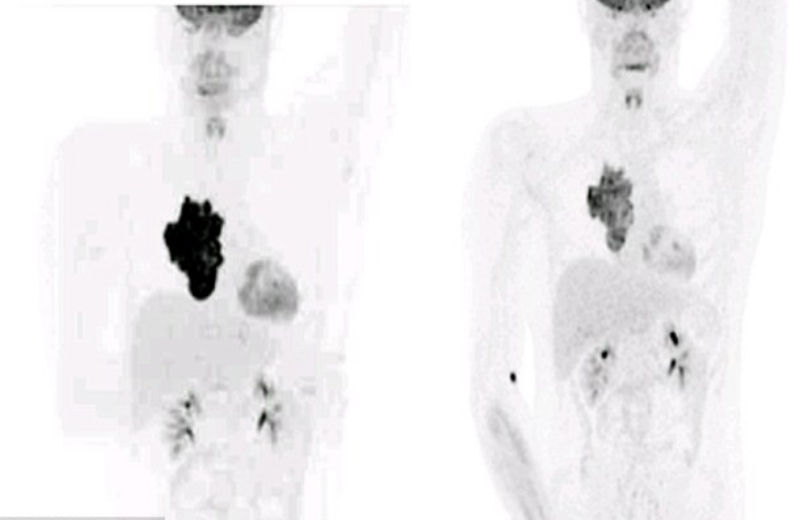

Agora o paciente linfoma, considerado terminal, compartilha incríveis fotos digitalizadas do encolhimento do tumor.

Agora, nove meses após o início do tratamento – que incluiu uma combinação de drogas e um transplante de células-tronco da irmã dele – o câncer praticamente desapareceu.

Na verdade, os médicos disseram que o tumor agora é tão pequeno que parece em remissão.

Key Eastwood, que é ex-estudante de mecânica, disse: “Depois de ver meus exames eu não podia acreditar como estava grande o tumor no meu peito”.

Veja as radiografias e a redução: